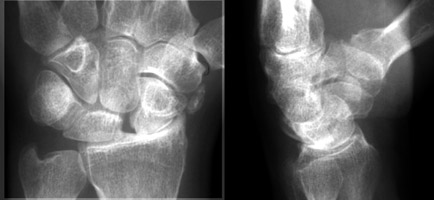

Multiple images of navicular disorientation with dislocation of the scapholunate joint. The scaphoid bone, seen along it long axis, has a ringed cortex appearance. This cortical ring sign is a sign of scapholunate dislocation, This sign was first described in 1970 in young patient with bilateral dislocation of the carpal naviculars. This sign (also known as the signet-ring sign) is caused by the abnormal orientation of the scaphoid.

- Click on the image for a larger versionA - Click on the image for a larger versionB